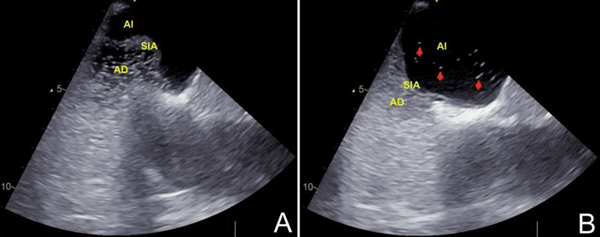

El ecocardiograma transtorácico (ETT) es usualmente la primera modalidad de imagen realizada. Con la imagen armónica se ha reportado una sensibilidad de 91% y una especificidad de 93% para el diagnóstico de FOP(7). A pesar de esto, existen inconsistencias entre los estudios y un bajo nivel de evidencia para los criterios diagnósticos. Es necesario el uso de contraste para demostrar el cortocircuito derecha-izquierda; es diagnóstica la presencia de más de una burbuja en la aurícula izquierda dentro de los primeros tres latidos. Sin embargo, la presencia de cortocircuitos pequeños o imágenes subóptimas puede limitar su eficacia, por lo que se prefiere la modalidad de ecocardiograma transesofágico (ETE) (figura 1). El Doppler color en el ETE ha registrado una sensibilidad y especificidad de 100% para detectar FOP(8). La academia estadounidense de neurología recomienda realizar ETE con contraste para detectar FOP y cortocircuito interauricular en el escenario agudo del ictus(9). El ultrasonido Doppler transcraneal con contraste puede detectar un cortocircuito de derecha a izquierda, pero tiene dificultades para ubicar su localización, por lo que puede ser usado en conjunto con el ETT y el ETE, para mejorar la precisión diagnóstica(10). Debido al bajo nivel de la evidencia, ningún estudio es considerado de elección, y en la mayoría de los casos el diagnóstico preciso de FOP necesita aunar los aportes de diferentes técnicas(6).

Ecocardiograma transesofágico: en la imagen A se observa la aurícula derecha (AD) con suero salino agitado. En la imagen B se aprecia el paso de burbujas (señaladas por las flechas) a la aurícula izquierda (AI). Al comparar las imágenes destaca la excursión desde la línea media mayor a 10 mm del septum interauricular (SIA).

Algunas características estructurales podrían predecir el riesgo de recurrencias de IC en pacientes con FOP. Estas características, que deben buscarse con detenimiento en el ETE, son el ASIA y el tamaño del FOP. El ASIA, cuya definición varía en los diferentes estudios, de forma general se refiere a la excursión del septum interauricular >10 mm desde la línea media. El tamaño del FOP se describe en base al cortocircuito derecha-izquierda, definido por el número de burbujas en la aurícula izquierda en menos de tres latidos cardíacos luego de la opacificación de la aurícula derecha con suero salino agitado. Aunque el número de burbujas usado para definir el tamaño varía de un estudio a otro, la mayoría de los autores usa un punto de corte de más de 10 burbujas(6,11). El estudio CLOSE(12) usó un número de más de 30 burbujas para definir un FOP como amplio, reportando que la recurrencia de IC en el grupo sin cierre percutáneo fue de 12,2% en los pacientes con ASIA y cortocircuito amplio, mientras que fue de 3,1% en los pacientes con FOP amplio sin ASIA.